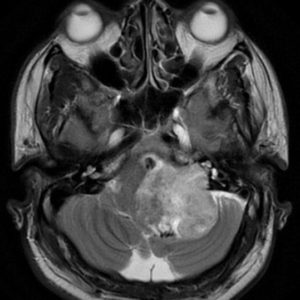

U dây VIII

Lượt xem: 132» 24-11-2018 -

U dây VIII

Lượt xem: 130» 24-11-2018 -

U dây VIII

Lượt xem: 153» 24-11-2018 -

U dây VIII

Lượt xem: 147» 24-11-2018 -

U dây VIII

Lượt xem: 117» 24-11-2018 -

U dây VIII

Lượt xem: 149» 24-11-2018 -

U dây VIII

Lượt xem: 143» 24-11-2018 -

U dây VIII

Lượt xem: 158» 24-11-2018